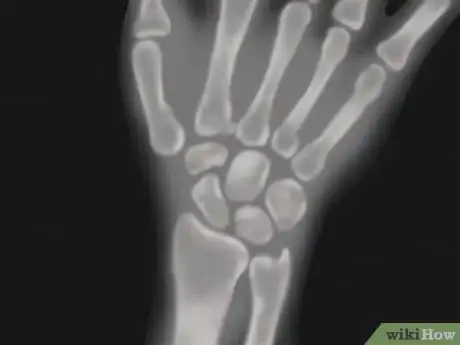

- X-rays, bone scans, MRI, and nerve conductance studies are modalities that your doctor may use to help diagnose your wrist issue. Your doctor may also send you for a blood test to rule out rheumatoid arthritis or gout.

- Children tend to have more fractures than sprains of the wrist.